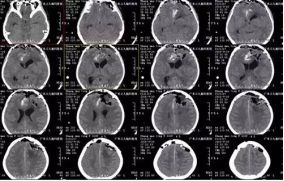

张女士,20岁,因间断头痛伴恶心、呕吐1年余,加重伴右侧肢体麻木1月,为求治疗,来我院就诊。入院后行头颅CT及MR示左侧额部大脑镰旁巨大脑膜瘤,大小约7.8×7.5×7cm,术前CTA提示肿瘤血管丰富,左侧大脑前动脉受挤压明显。由于瘤体太大,为保证患者的手术安全,经科室专家讨论研究决定,择期全麻下为患者行“左侧额部大脑镰旁巨大脑膜瘤切除术”,手术由张良主任主刀完成。经手术、术后康复理疗、物理治疗等系统的治疗后患者症状消失,康复出院。

↑术后检查